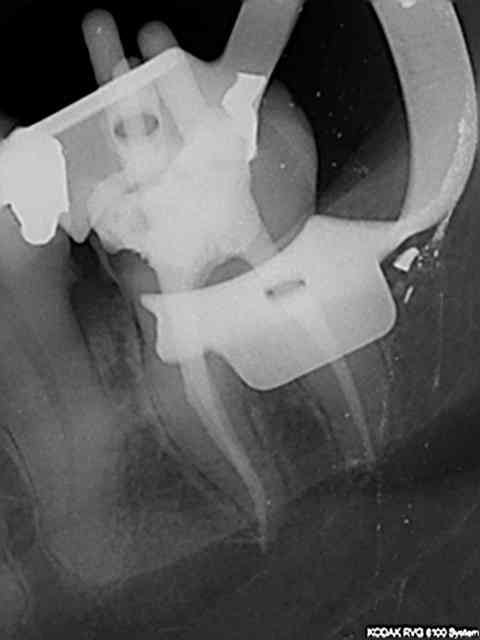

Pour débuter achètes le coffret de clamps FIESTA 9 de chez hygenic. Pour la digue optidam de chez kerr avec les cadres correspondants. Cette digue est préformée à la forme de la cavité buccale et ne pose donc pas de problèmes pour les radios que tu peux faire sans retirer le cadre (capteur trophy pas de problème par ex), autre avantage , les tétons à la place des dents que tu découpes au ciseau. Préférer les crampons à ailettes car tu peux soit enfiler la digue dessus crampon en place soit les mettre sur la digue et mettre le tout en place. on est souvent gèné, (crampon en place) par la dent en distal en enfilant la digue toutefois,;

Durée de la mise en place : 30 s maxi. Un jeu meme pour cette 38 par exemple.